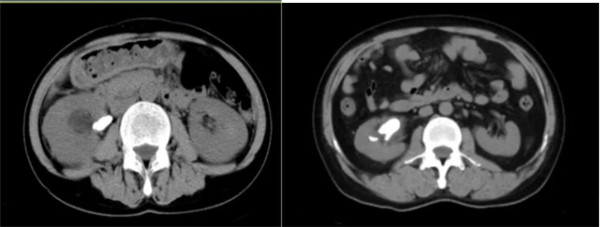

宝鸡市人民医院泌尿病院每年诊治各类泌尿系结石患者近万人次,擅长各种复杂性泌尿结石的诊断及手术治疗。以上2名均系肾结石患者,其结石体积较大,数 目较多,手术难度相对较大,两名主任在给予准确的定位后,皆1针见尿,结合EMS碎石系统,碎石效率高,并附带负压吸引功能,清石效率大幅提高,大大缩短了手术时间,手术几乎做到了“零出血”,有效地减少了手术并发症的发生,手术得到了种铁主委及各位点评专家的一致认可。